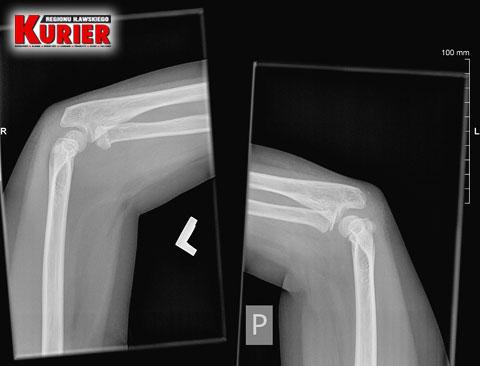

| 38969. | LECZENIE METODĄ NA... MILCZENIE

Ból 8-letniego dziecka zmusił matkę, by po pomoc pojechała do szpitala w Nowym Mieście, bo w Iławie powiedziano jej, że bolący łokieć synka to „tylko stłuczenie”. Skończyło się operacją aż w Olsztynie i stabilizacją stawu drutami. Teraz chłopiec poddawany jest kosztownej rehabilitacji.

Co na to iławski szpital? Od ponad 2 miesięcy milczy.

https://www.kurier-ilawski.pl/czytaj/Leczenie-metoda-na-milczenie/5282 |